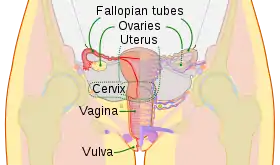

Schematic frontal view of female anatomy

Schematic frontal view of female anatomy